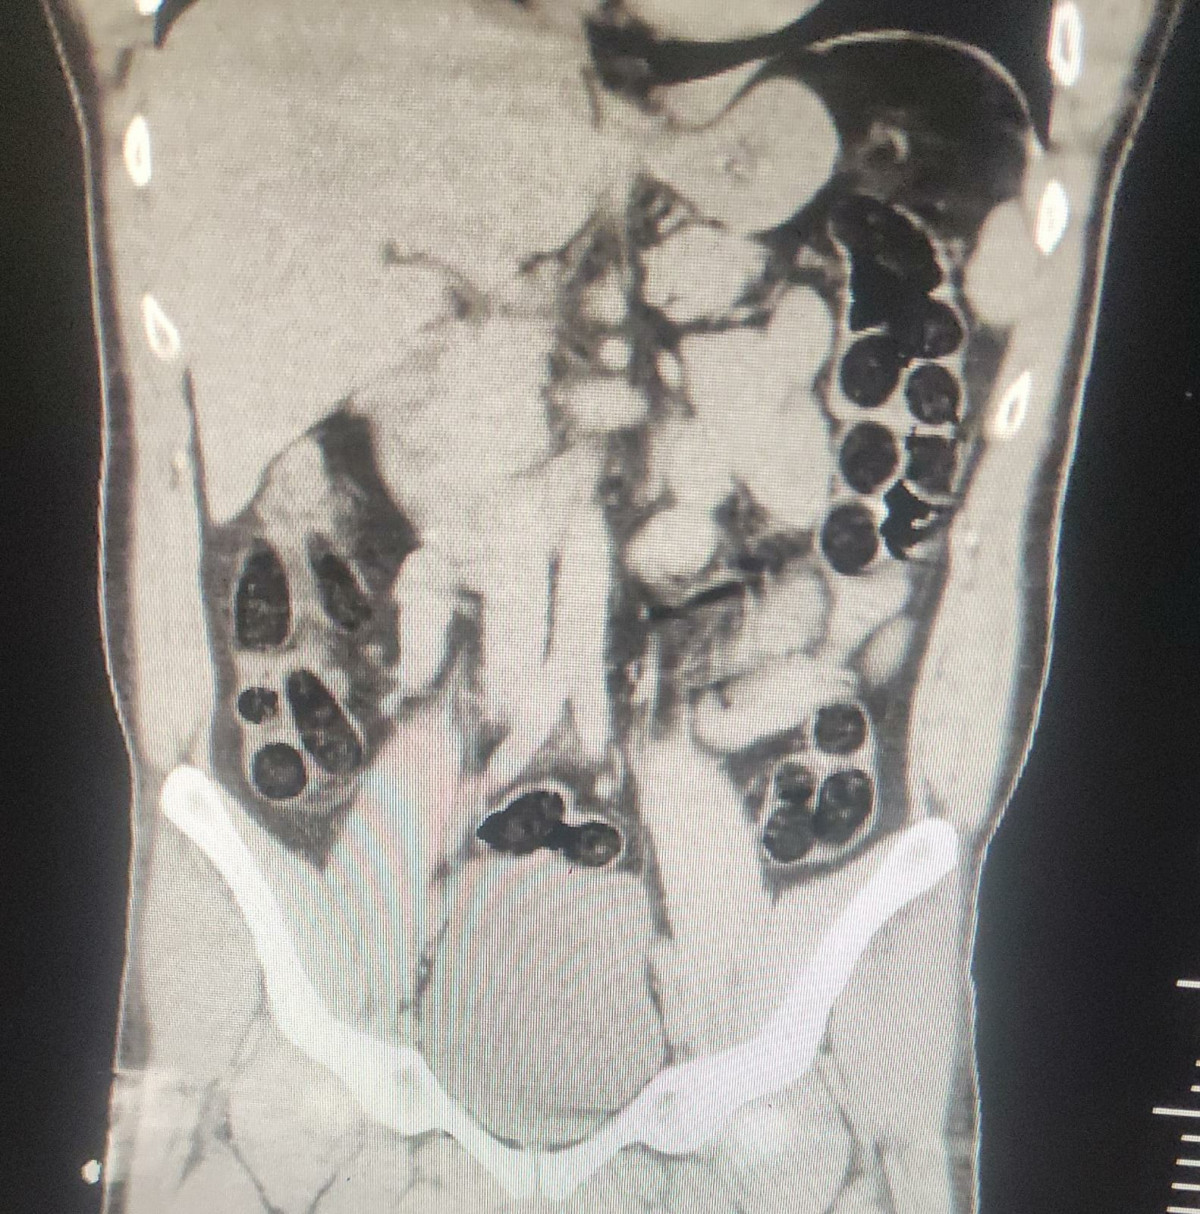

Hastanede çekilen röntgenlerinde birinin midesinde uyuşturucu tespit edildi. Şüphelinin, 76 paket halinde 714 gram eroini doğal yollarla çıkarılması sağlandı.